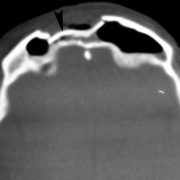

- Examination shows depression of the mid-forehead with associated minor lacerations, extensive abrasions, and edema. CT scan shows a comminuted frontal sinus fracture with involvement of both the anterior and posterior walls. There is extension into a frontoparietal skull fracture. Pneumocephalus is also noted and a CSF leak is suspected.

- Treatment consists of a coronal approach with debridement and cranialization. Neurosurgery assists with the debridement of the comminuted posterior wall and repairs two tears in the dura. The anterior wall is repaired with microplate fixation and a persistent defect is reconstructed with a split calvarial bone graft. All of the frontal sinus mucosa is removed, and the nasofrontal ducts are obliterated. At the conclusion of the repair, there still is persistent dead space between the reconstructed anterior wall and the dura. This is obliterated with a free fat graft.